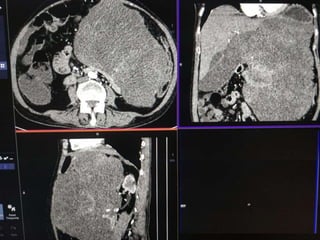

 55 yr old female patient

 Presented with complaints of lump abdomen and vague

abdominal discomfort

 Bowel habits normal with no other gastrointestinal complaints

CASE 2

CASE2

DIFFERENTIALS

Diagnosis Points in favour Points against

Retroperitoneal

sarcomas

• Leiomyosarcoma

/Undifferentiated

Liposarcoma

• MFH

Age and clinical

presentation

Imaging features

(Large ill defined

heterogeneously

enhancing lesion

with areas of

necrosis)

No fat density/

calcification

No calcification

GIST Age

Biopsy:

 Poorly differentiated Leiomyosarcoma